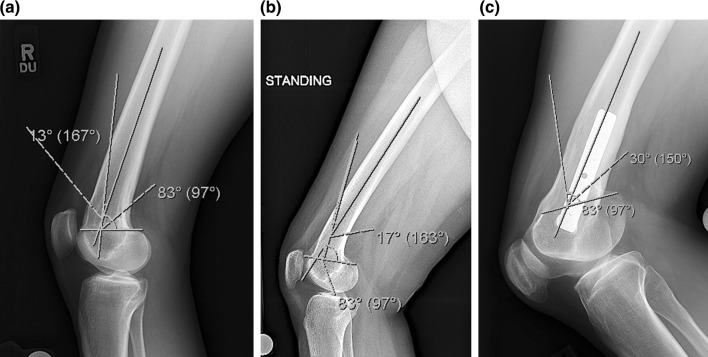

Fig. 2.

a The lateral radiograph of patient 1 shows the apex of deformity lies just proximal to the posterior condyles and has a magnitude of 13°, b the lateral radiograph of patient 2 shows the apex of deformity lies slightly more proximal than patient 1 and has a magnitude of 17°, c the lateral radiograph of patient 3 shows the apex of deformity lies at the level of the posterior condyles and has a magnitude of 30°